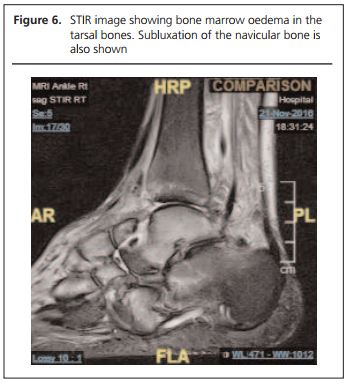

At review a month later he reported that he heard a crack in his right foot the week before and he had attended the ortho-paedic clinic (Figures 3 and 4). His foot X-ray showed changes of Charcot neuro-osteoarthropathy in the midfoot (Figure 5). The swelling in his right leg had gone down and the swelling in his right foot had also improved, but the right foot remained warmer than the left. He was put in a non-removable below-knee cast. The MRI foot scan which we had requested when we saw him in clinic initially had been performed two days before his clinic appointment and this confirmed active Charcot neuro-osteoarthropathy (Figure 6). He remained in a cast for six months until the temperature difference between the feet was less than two degrees (Figure 7).

2017-11-Gohil_Figure_6